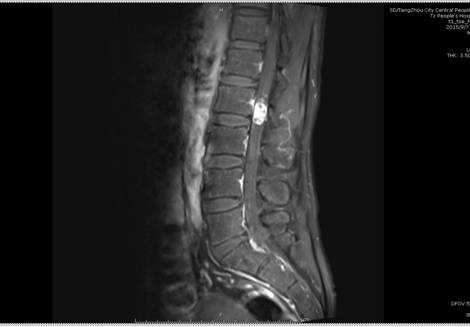

患者李某,男,40歲,因“右下肢疼痛、麻木8年余,伴腰部疼痛、活動受限1年余”入院,入院前患者曾在外院就診診斷為右側股骨頭壞死,一直予口服中藥治療,癥狀不見好轉,近1月來癥狀明顯加重。來我院行腰部MRI檢查示L2椎體水平椎管內占位,考慮良性神經源性腫瘤;L5/S1椎間盤突出;腰椎退行性變。神經外二科主任續繼軍帶領團隊仔細評估患者術前狀態,多次進行病例討論,認為患者手術指征明確,但手術風險較大,容易引起下肢癱瘓、大小便失禁等并發癥?;颊哒登鄩涯?,為家庭中支柱,一旦喪失勞動力,對整個家庭將是災難性打擊。

術前影像學檢查